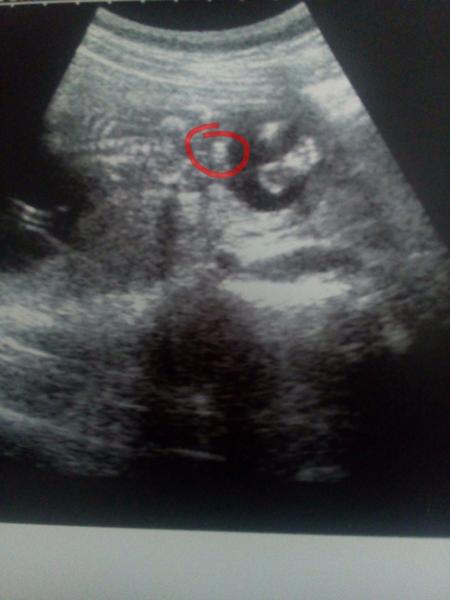

Je to holčička nebo chlapeček? Foto ultrazvuku

Ahoj maminky a budoucí maminky 😉 Prosím, poradila byste mi některá, co vidíte na fotce z ultrazvuku ve 20. týdnu za pohlaví? Určitě jste foteček viděly už mraky, proto vás žádám o radu...Nechci nikoho ovlivnit, proto svůj tip řeknu později 🙂 Děkuju moc!!!

@maxinkaa miminko je zády to v kolečku je něco snad pohlaví 🙂

dle gynekologie se přiklání k holce,ale pořád je špatně natočené 🙂

Holky , tak přidávám fotku z 20tt, měl by to být detail pohlaví🙂 Tak hádejte po druhé🙂

@estrellita Taky? Fakt?????? Všechny vidíte pinďu😀 Tak uvidíme, snad DR, dnes něco uvidí, dám si Colu, aby to bylo vzhůru. Pokud pinďa, tak takový ten výběžek uprostřed? jedna noha, druhá noha a uprostřed pinďa? To bych taky asi tak viděla.

Mě na té spodní fotce, kde jsou vidět ty nožičky, právě připadá, že ,,to'' uprostřed by u kluka mělo být jakoby víc do špičky, že z tohoto úhlu to sice vyčnívá, ale ony i ty pohlavní výběžky u holčiček jsou někdy takhle vidět 🙂. Tak jsem sama napnutá!

@zuzkabrhelova nejdou mi z mobilu opravy,tak ten komentar s briskem by byl k fotce @anonym1987 ,jestli je to tedy zespodu brisko cele a pohlavi,tak to muze byt i kluk a pindik visi smerem dolu🙂 takze 50:50